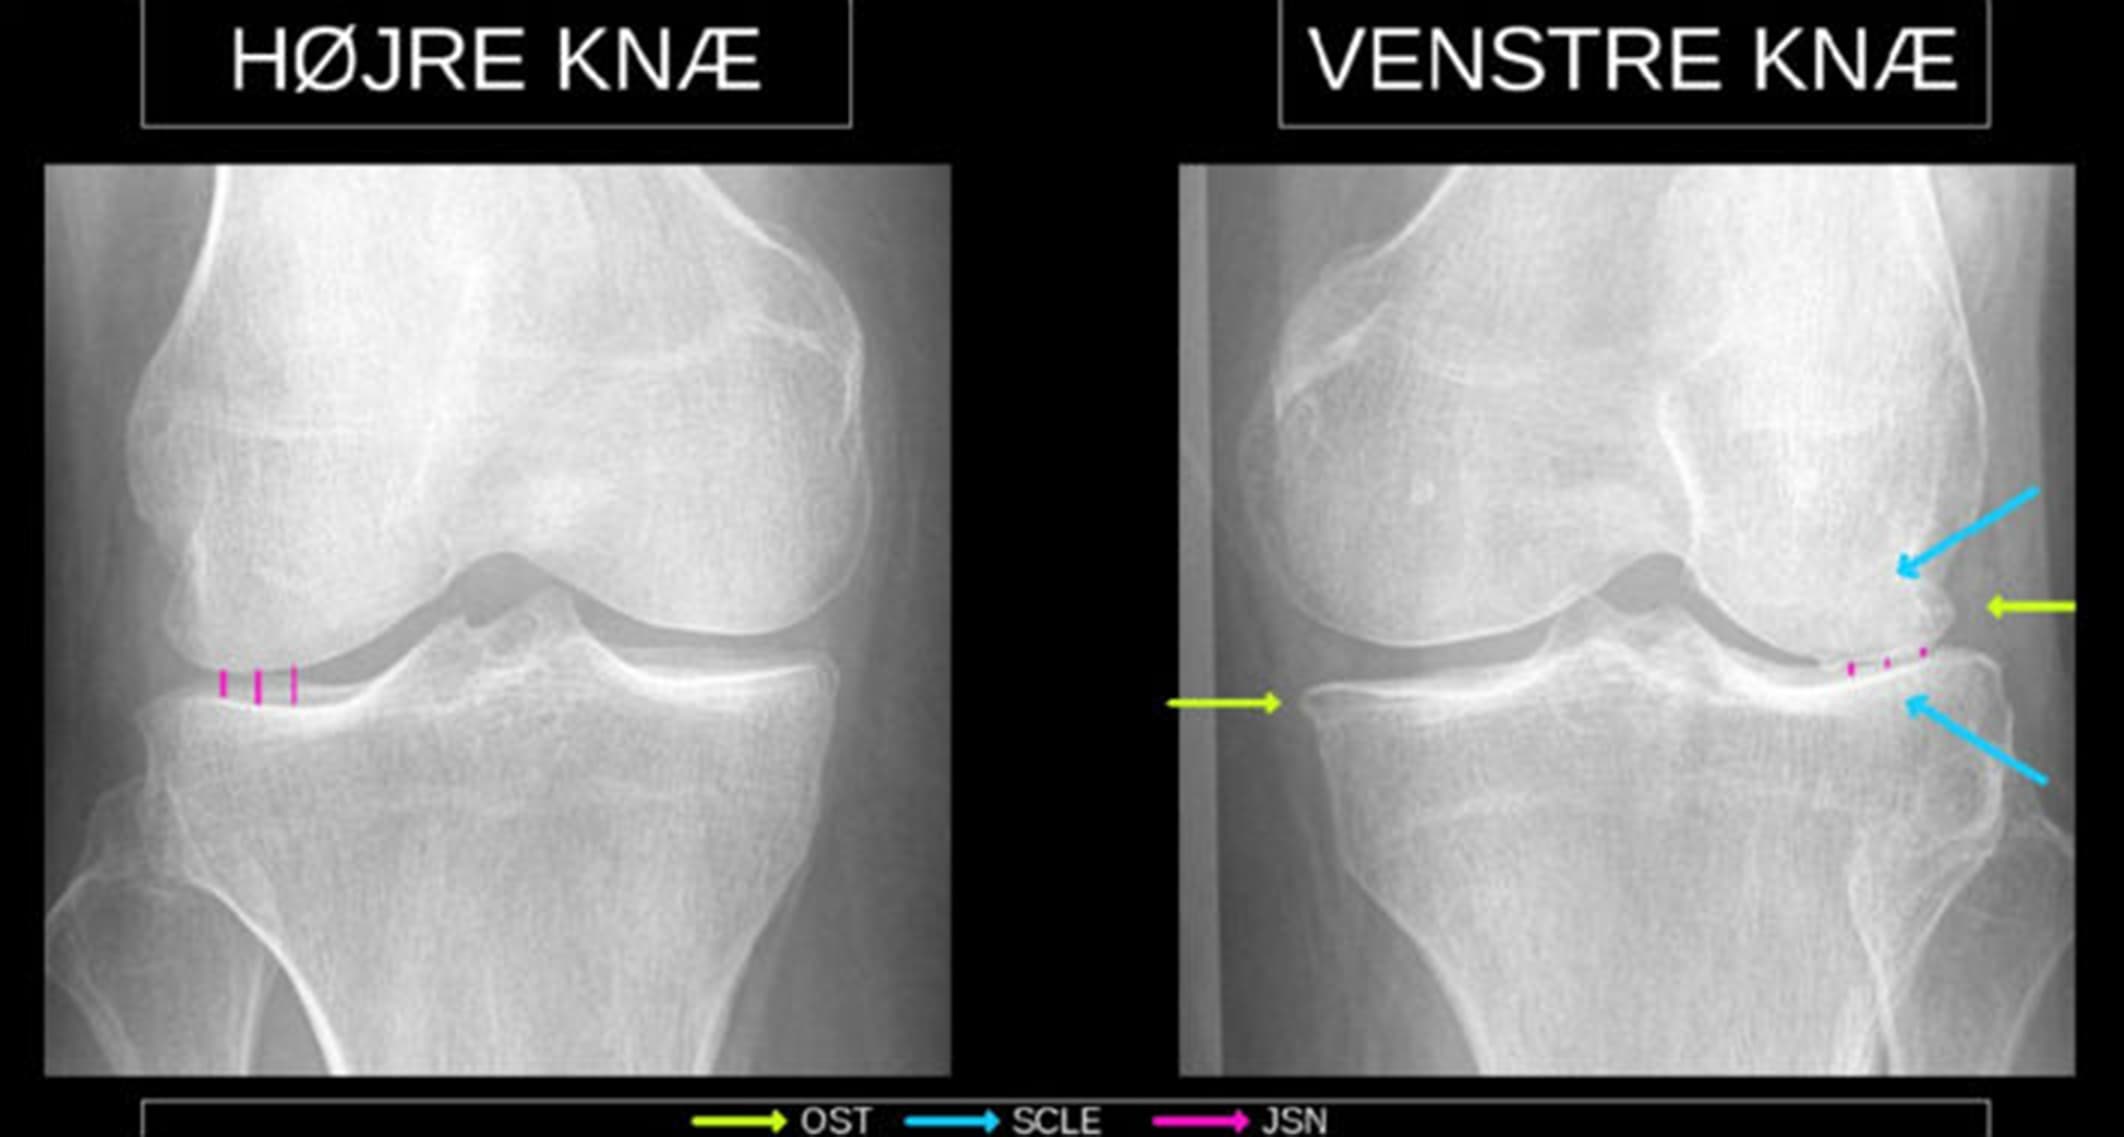

Røntgenbillede af knæ med slidgigt taget bagfra. Grafisk tilføjes det eksisterende originalbillede pile og streger for at fremhæve de relevante sygdomstegn. Ved hjælp af algoritmen kan man automatisk beskrive graden af slidgigt på røntgenundersøgelsen af knæ på samme høje niveau, som en erfaren radiolog. Visionen er, at teknologien med signaturprojektet bliver rullet ud til alle regionens hospitaler.